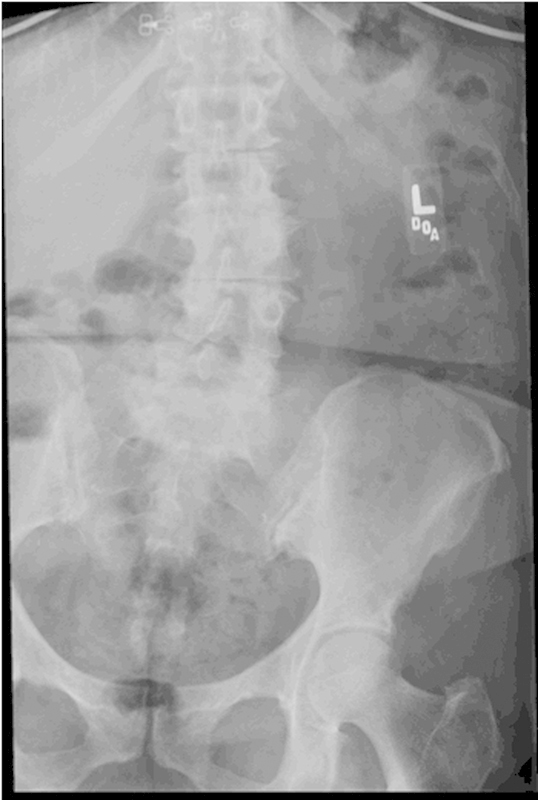

研究设计案例报告。目的本研究的目的是提出一个不寻常的情况下,59岁的妇女与复发的无菌术后血清肿。方法术后观察1例患者在创面闭合前先在软组织内放置预防性万古霉素粉2 g (1 g与后外侧骨融合术联合使用,1 g放置于软组织内)进行多节段腰椎前后路融合术的并发症或不良反应。在初始手术后的6个月内监测患者的进展。术后6周,患者摔倒,疼痛加重。磁共振成像、计算机断层扫描和x线显示骶骨骨折移位,大量硬膜外积液,腰椎手术部位硬膜囊严重受压(L3-5)。结果根据上述影像学检查和患者进行性神经功能缺损,在6周的随访中明显需要紧急手术干预。引流和检查硬膜外积液,同时治疗移位性骶骨骨折(S1-S2)。患者术后过程平稳,背部疼痛和神经功能障碍得到缓解;然而,复发的硬膜外积液需要连续穿刺混淆了患者的临床表现。结论由于该血肿的复发性不常见,其液体收集和形成的原因尚不清楚。由于缺乏骨形态发生蛋白的使用,并且很少有可解释的混杂变量,对局部万古霉素粉末的急性过敏反应是可能的病因。建议对更大的患者群体进行分析,比较预防性万古霉素粉末的术后不良反应。

Study Design Case report. Objective The objective of this study was to present the unusual case of a 59-year-old woman with a reoccurring sterile postoperative seroma. Methods A patient was observed postoperatively for any complications or adverse side effects resulting from an initial multilevel anterior/posterior lumbar fusion surgery where 2 g (1 g combined with the bone graft used for posterolateral fusion and 1 g placed in the soft tissues) of prophylactic vancomycin powder was placed within the soft tissues posteriorly before wound closure. The patient's progress was monitored through 6 months following the initial procedure. Six weeks postoperatively, the patient sustained a fall and had increased pain. Magnetic resonance imaging, computed tomography, and X-rays demonstrated a displaced sacral fracture, a large epidural fluid collection, and severe compression of the thecal sac at the lumbar operative sites (L3-5). Results On the basis of the aforementioned imaging studies and the patient's progressive neurologic deficit, it was apparent at the 6-week follow-up that emergent surgical intervention was necessary. Drainage and examination of an epidural fluid collection along with treatment of a displaced sacral fracture (S1-S2) were performed. The patient had an uneventful postoperative course with resolution of her back pain and neurologic deficit; however, recurrence of the epidural fluid collection requiring serial aspirations confounded the patients' clinical presentation. Conclusions With the recurrent nature of the seroma being unusual, the cause of the fluid collection and formation is undetermined. With lack of bone morphogenetic protein usage, and few confounding variables accountable, an acute allergic response to topical vancomycin powder is a possible etiology. Analysis with larger patient populations comparing postoperative adverse effects of prophylactic vancomycin powder is recommended.